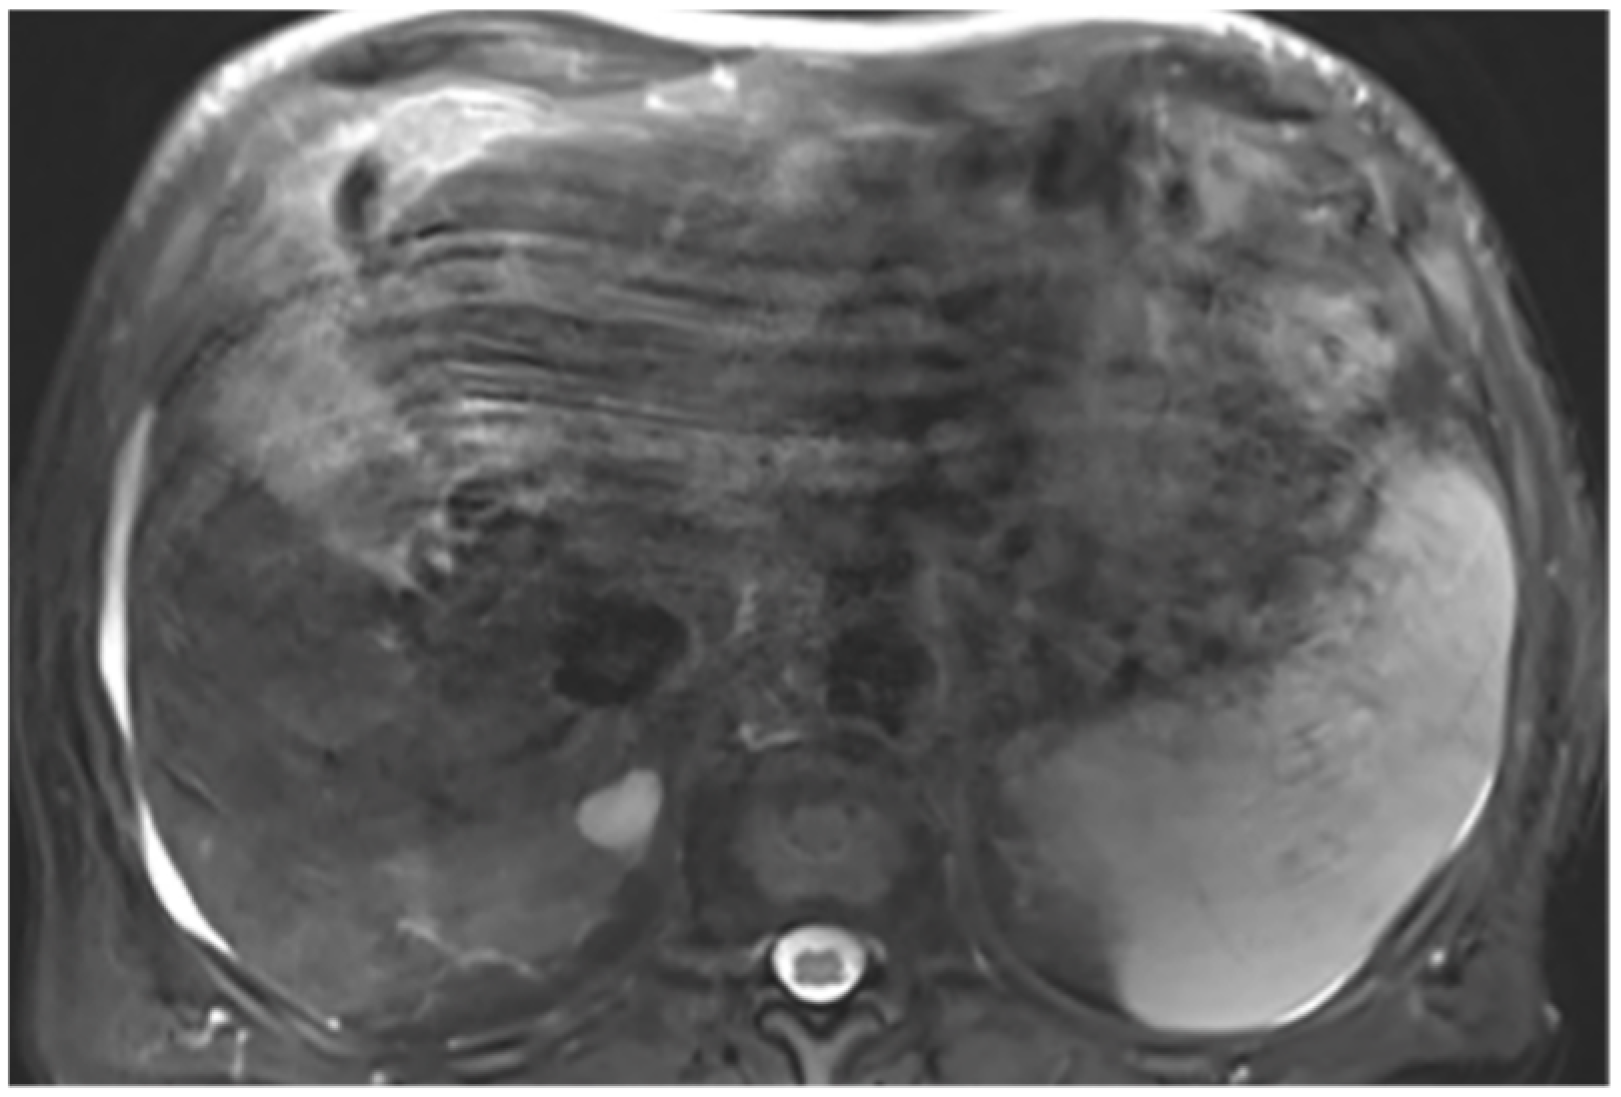

2.2. Liver Segmentations and Protocol

Appendix A.6. Presence of Respiratory Artifacts